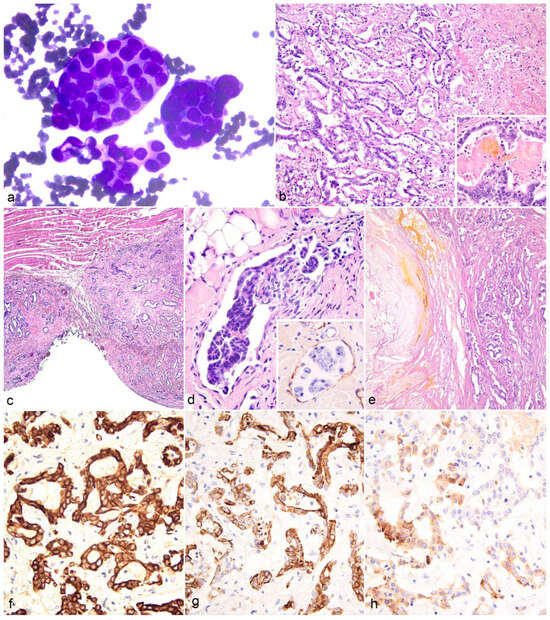

2.3. Cytological, Histological, and Immunohistochemical Findings